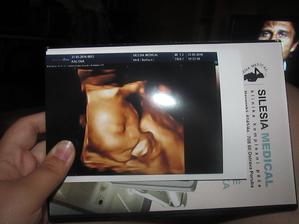

Klokan přiletí v září

jééé, krásný bobišek 😉 a už takový velký...